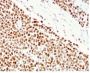

Applikationen WB, FC, IF, IHC

Flow, intracellular (verified), IF (verified), IHC, FFPE (verified), WB (verified)

Positive Control

HCT116 or HeLa cell lysate (WB). Human colon carcinoma (IHC).

Antibody target cellular localization

Nucleus